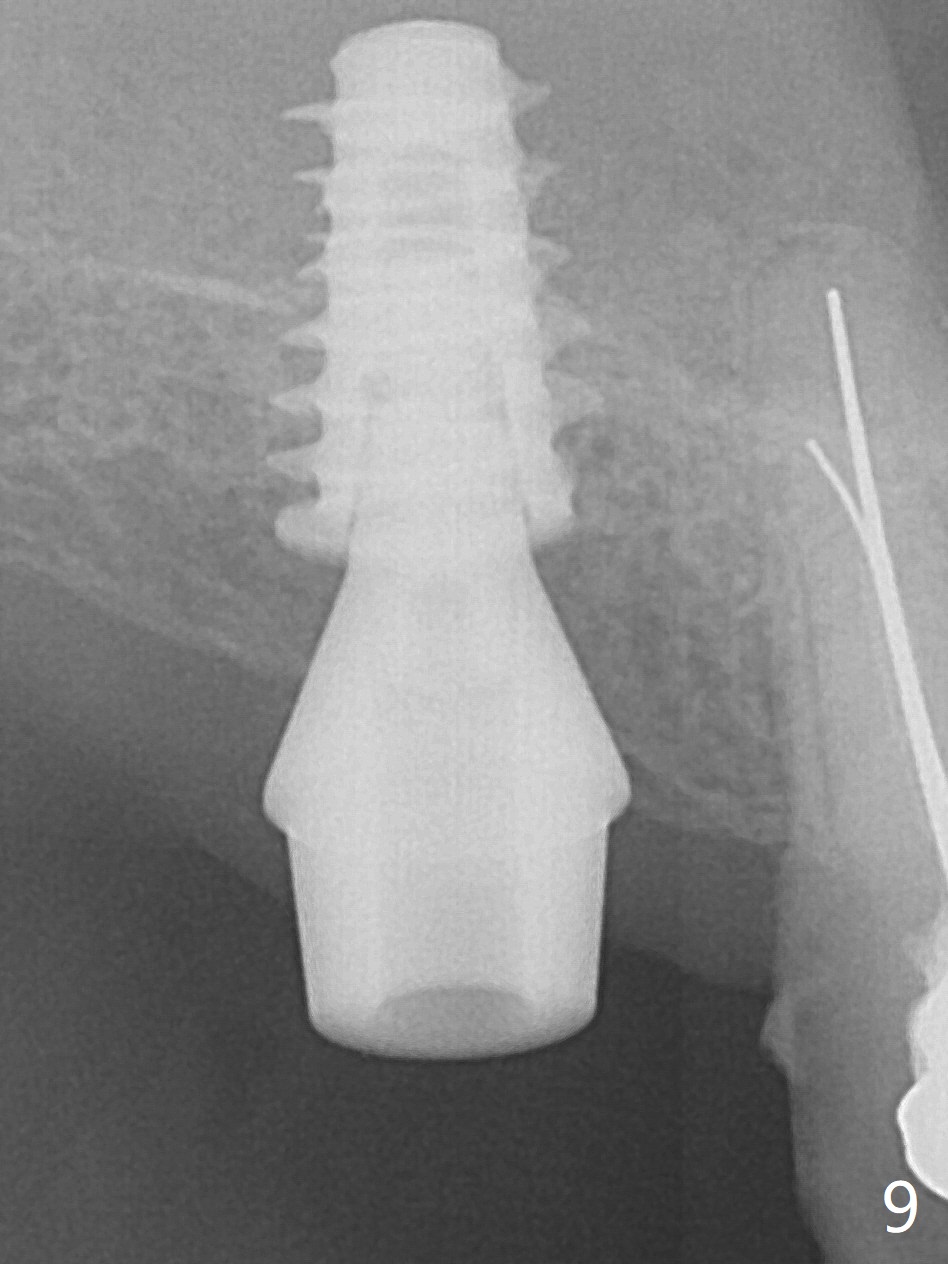

Since the ridge is wide at the site of #2, Magic Split is used for access (flapless) and bone expansion. The bone is so soft that there is no resistance until 4.3 mm Magic Expander is used for 9 mm (Fig.6). A 5 mm tap drill is stable (Fig.1), so are a 5.5x9 mm dummy implant (Fig.2) and a 6x9 mm IBS implant (Fig.3 (<: sinus lift)). In fact the distal thread is still supracrestal (Fig.4 (BW)). After additional 2 mm placement, the distal thread is subcrestal (Fig.5); the mesial margin of a 6.5x4(4) mm abutment is subgingival. A longer cuff (5 mm instead of 4 mm) is more favorable for future restoration. At present the abutment (Fig.7) as well as the tooth #3 with rugged surfaces is used to hold periodontal dressing in place. The abutment margin is completely subgingival 3 months postop (Fig.8 (white dashed line: gingival margin)). It appears that the implant is placed ~ 1 mm deeper than ideal (Fig.9). Diode laser is used for gingivectomy prior to impression. The abutment screw becomes loose 2 months post cementation. After retightening, occlusal equilibrium is conducted with 3 layers of articulating paper. Night guard is provided. The crown/abutment dislodges 1 year 2 months later. Since the gingiva is erythematous, a 6x7 mm healing abutment is placed (Fig.10). The implant seems to have been placed too deep and palatal. It appears that an abutment driver should be buried to prevent the screw re-loosening. Guided surgery should have been done.